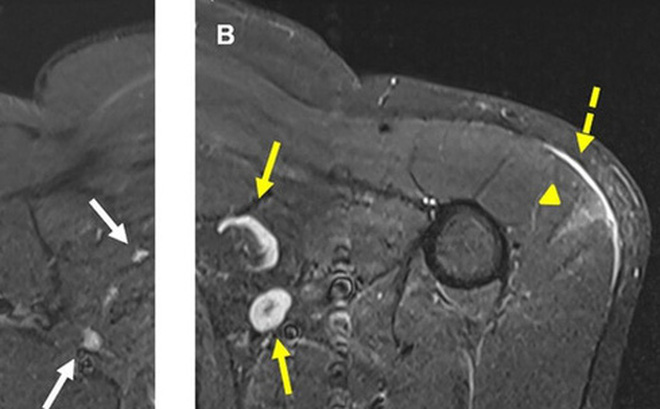

Tuy nhiên, hạch bạch huyết có thể hiển thị dưới dạng đốm trắng trên kết quả chụp quang tuyến vú hoặc chụp cắt lớp lồng ngực, gần giống với hình ảnh lây lan của khối u. Các chuyên gia X-quang cho rằng con số thực tế có thể cao hơn, nhiều trường hợp hiển thị trên ảnh chụp quang tuyến vú, cắt lớp hoặc CT.

Tiến sĩ Constance D. Lehman, trưởng khoa Phân tích Nhũ ảnh tại Bệnh viện Đa khoa Massachusetts, tác giả của hai báo cáo đăng trên tạp chí Roentgenology về vấn đề này, cho biết: "Tôi đặc biệt muốn phổ biến điều này đến các bệnh nhân đang theo dõi sau khi điều trị thành công ung thư. Họ có thể lo lắng khi tái khám và nghe được rằng bác sĩ tìm thấy một đốm trắng lớn, có thể là dấu hiệu của ung thư’".

Theo bà Lehman, điều quan trọng là các trung tâm chẩn đoán hình ảnh cần nắm được thông tin người bệnh đã từng tiêm phòng COVID-19 hay chưa? ghi lại ngày và vị trí tiêm. Đối với các bệnh nhân khám sàng lọc có đốm trắng trên kết quả chiếu chụp nhưng không gặp vấn đề bất thường nào khác, phòng khám của bà gửi kèm thư lưu ý: "Hạch xuất hiện ở vùng nách bên tiêm vaccine COVID-19 lớn hơn, có hiển thị trên ảnh chụp quang tuyến vú. Điều này rất phổ biến, là phản ứng bình thường của cơ thể với vaccine. Tuy nhiên, nếu cảm thấy có khối u ở nách kéo dài hơn 6 tuần sau khi tiêm phòng, bạn nên thông báo lại với bệnh viện".